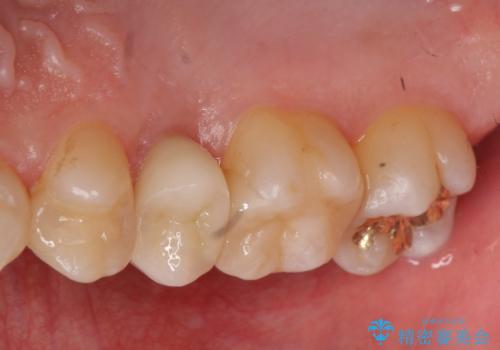

放置した虫歯 歯ぐきの中まで虫歯でも、しっかり健康的な部分を引っ張り出して、きちんと処置します。

- 放置した虫歯の治療で来院。

歯茎の中まで虫歯になっており、そのまま完璧に治療をすることは不可能でした。

開始前